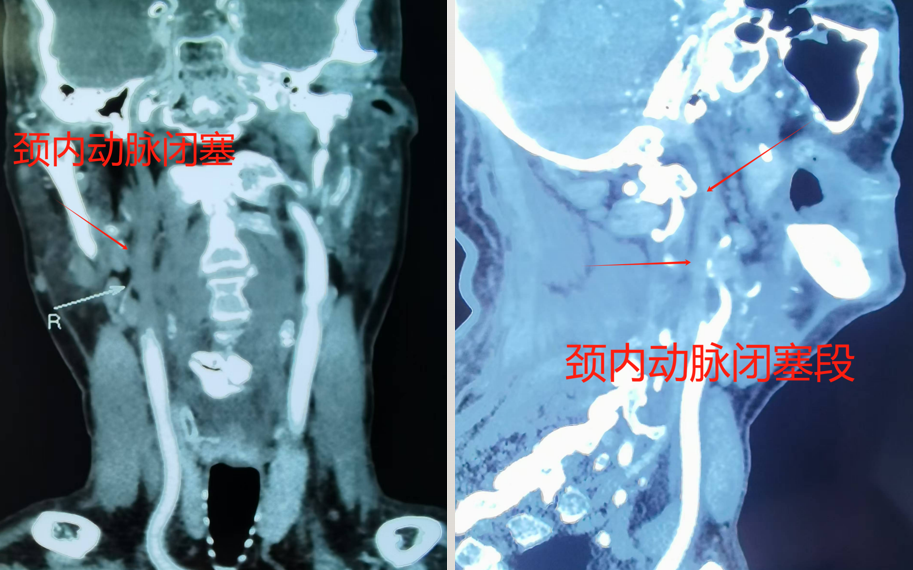

脑血管造影很快结束,确定了姜老先生是因右侧颈动脉闭塞导致了一系列症状。姜昊主任详细评估并与患者家属充分沟通后,决定为姜老先生行颈动脉慢性闭塞介入再通术。